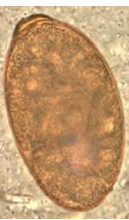

Eggs that look like this were found on a fecal flotation of a dog presenting with hemorrhagic enteritis & other signs similar to canine parvovirus. What etiologic agent is responsible for the clinical signs?

Neorickettsia helminthoeca